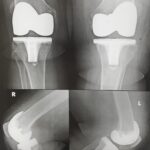

The goal of total knee replacement surgery is to relieve pain and restore the alignment and function of your knee.

The surgery is performed under spinal or general anesthesia. Your surgeon will make an incision in the skin over the affected knee to expose the knee joint. Then the damaged portions of the femur bone are cut at appropriate angles using specialized jigs. The femoral component is attached to the end of the femur with or without bone cement. The surgeon then cuts or shaves the damaged area of the tibia (shinbone) and the cartilage. This removes the deformed part of the bone and any bony growths, as well as creates a smooth surface on which the implants can be attached. Next, the tibial component is secured to the end of the bone with bone cement or screws. Your surgeon will place a plastic piece called an articular surface between the implants to provide a smooth gliding surface for movement. This plastic insert will support the body’s weight and allow the femur to move over the tibia, similar to the original meniscus cartilage. The femur and the tibia with the new components are then put together to form the new knee joint. To make sure the patella (knee cap) glides smoothly over the new artificial knee, its rear surface is also prepared to receive a plastic component. With all the new components in place, the knee joint is tested through its range of motion. The entire joint is then irrigated and cleaned with a sterile solution. The incision is carefully closed, drains are inserted and a sterile dressing is placed over the incision.